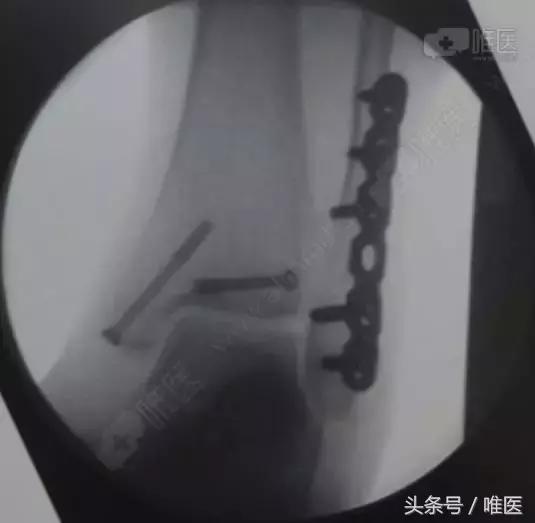

全身麻醉成功后,取左侧卧位,右下肢常规消毒铺巾,右外踝后外侧切口长约8cm切开皮肤、深筋膜,自拇长屈肌及腓骨长短肌间隙进入,暴露外踝及后踝骨折块,复位后踝骨折块后予克氏针临时固定,纠正腓骨远端骨折外移及短缩畸形,克氏针临时固定,透视外踝及后踝骨折复位良好,取合适长度的后侧解剖锁定钢板螺钉牢固固定外踝,空心螺钉固定后踝,再次透视骨折复位及内固定位置良好,冲洗缝合外侧伤口,取仰卧位,右内踝弧形切口切开暴露内踝骨折块及内侧间隙,术中见内踝骨折移位,内侧间隙内碎骨块游离,清理内侧间隙,复位内踝骨折后予导针固定,透视骨折复位及导针位置良好,取34mm长度的4.0 空心螺钉牢固固定,透视骨折复位及内固定位置良好,冲洗伤口,缝合,术中出血约100ml,未予输血。术中伤口予罗哌卡因+得宝松局部镇痛治疗。手术顺利,病人送PACU。